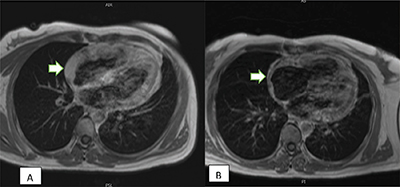

Figure 3

(A) Post-contrast T1 imaging before the treatment; (B) Post-contrast T1 imaging following chemotherapy treatment reveals a partial response with decreased tumor thickness (arrow).